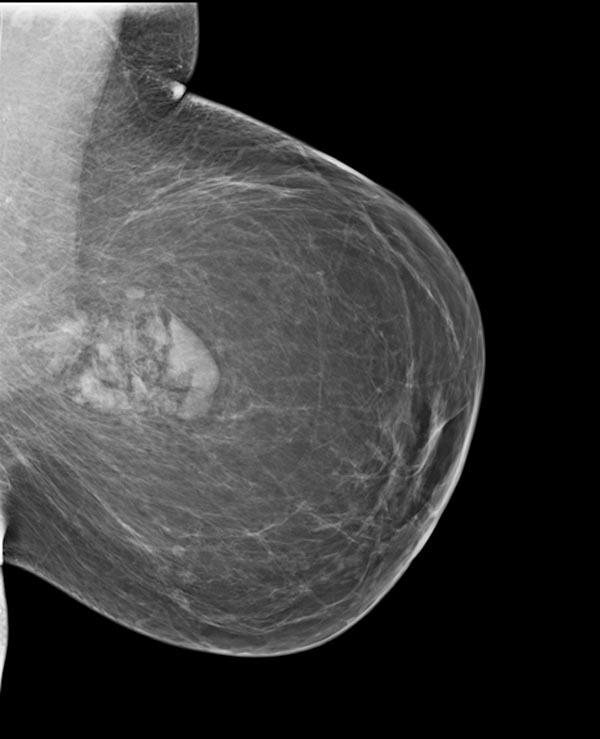

What are the characteristic mammography findings of a hamartoma?

1) Circumscribed area of soft and lipomatous tissue

2) Surrounded by thin radiolucent zone